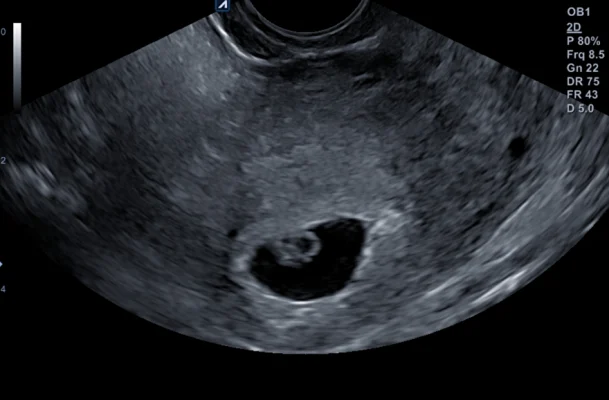

Na een paar zenuwslopende weken mochten we dan eindelijk naar de verloskundige voor de eerste echo. Normaal doen ze eerst een gesprekje maar ik kwam al huilend binnen, hier hing alles vanaf voor mij! De verloskundige reageerde erg empathisch en ze zei: “Zullen we maar eerst een echo maken dan?”. Heel fijn! En heel eng! “Sorry het wordt wel inwendig omdat het nog zo vroeg is”. Inmiddels had ik zoveel inwendige echo’s gehad dat ik verbaasd was dat ze sorry zei! Maar goed…daar gingen we….even zoeken..en JA!!! Een kloppend hartje!!! Ik was nog steeds aan het huilen sinds binnenkomst dus dat ging

mooi in een ruk door! Het zag er allemaal goed uit! De opluchting die je dan voelt, ontlading, blijdschap, het verdriet dat je hebt gehad, de onzekerheid, zoveel…het is met geen pen te beschrijven.